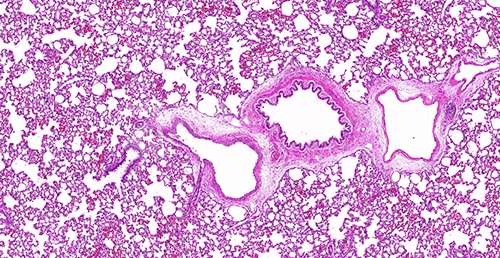

肺纤维化是一种严重影响人类健康的疾病,其特征是肺组织中纤维结缔组织的过度增生和沉积,导致呼吸功能受损。为了深入研究肺纤维化的发病机